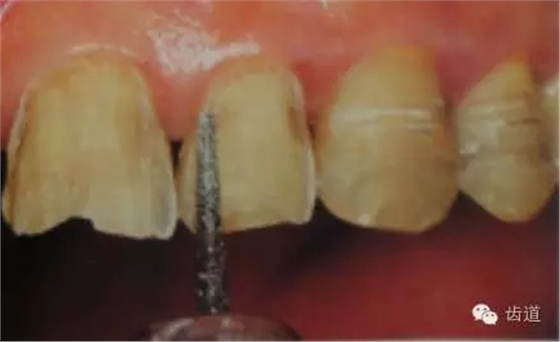

1、唇面預(yù)備:先用定深車針定出定深溝,再換合適車針磨除剩余的釉質(zhì)。

唇面磨除的量依據(jù)所用貼面材料及牙齒的變色程度而定。

如下圖: